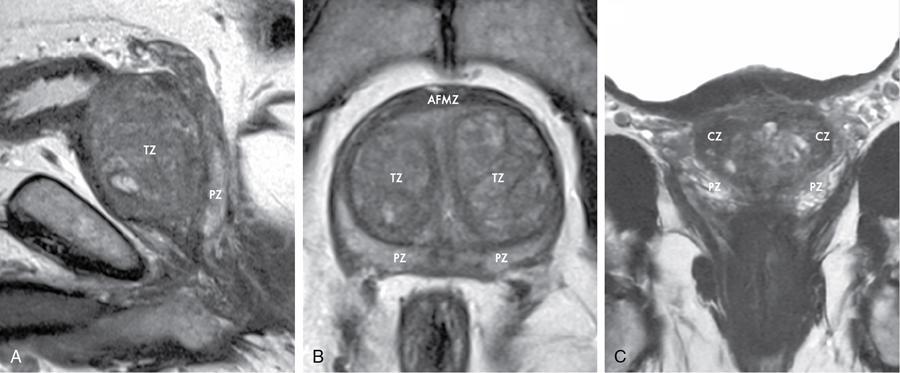

Karthik Ganesan, Disha Lokhandwala, Ujjwal Bhure, Jay Mehta Morphogenesis of the male genitourinary system is governed by the coherent interaction of three units, namely the Wolffian duct, urogenital sinus and foetal gonads. The Wolffian ducts are the embryonic precursors of the male internal genitalia, arising in the anterior intermediate mesoderm at 4 weeks of gestation. They elongate as a cord of cells that caudally extend to the urogenital sinus. Between 5 and 8 weeks of gestation, the urorectal septum divides the cloaca into a ventral compartment, which forms the urogenital sinus, and a dorsal compartment, which forms the rectum. The gonads form as epithelial thickenings on the ventromedial surface of the mesonephros and produce testosterone at 8 weeks of gestation, reaching a peak at 10–15 weeks. Under the effect of testosterone produced by the foetal testis, the prostate anlage forms at the tenth week of gestation. Precursor of the anlage begins with proliferation of solid epithelial buds from the epithelium of the urogenital septum into the adjoining mesenchyme in response to interaction of 5α-dihydrotestosterone with mesenchymal androgen receptors. As growth progresses, solid cords of epithelial cells are formed, growing into the mesenchyme in a specific three-dimensional arrangement (establishes the lobar divisions of the prostate gland). These solid cords develop a central lumen at birth and are lined by a layer of flat basal epithelium and a luminal layer of tall columnar secretory epithelium. Mesenchymal component forms the stroma, which has a large proportion of smooth muscle. Postnatally, the epithelial cords continue to arborize till puberty without any change in volume or glandular architecture. Although the foetal prostate has been described to have a histologically distinct peripheral zone (PZ) as early as 12 weeks of gestation, the mature zonal anatomy develops in concordance with the androgen surge at puberty. The most commonly utilized ultrasonographic technique for the evaluation of the prostate is via a suprapubic approach. The abdominal transducers used in this approach are relatively low frequency and while it offers the advantage of greater depth of penetration without intracavitary probe insertion; however, it does not depict the zonal anatomy and its chief application lies in volume estimation. Hence, transrectal ultrasonography (TRUS) completely outweighs the transabdominal approach in terms of depicting zonal anatomy, visualizing and localizing small lesions, demonstrating vascularity and performing biopsies. TRUS is performed using high frequency transducers (5–7.5 MHz) to optimize soft tissue resolution. An enema is administered 1 h prior to the examination to clear the field of insonation. Patient is positioned in left lateral decubitus, with knees bent toward the chest and ideally a digital rectal examination (DRE) is conducted prior to probe insertion. The transducer is first draped with a sterile barrier and lubricated, After insertion, the barrier is filled with 40–50 cc of water, making sure that no air enters. On completion, water is aspirated and the probe is withdrawn. The gland is initially scanned in the axial plane from the base to the apex, beginning at the level of the seminal vesicles, and the probe is gradually withdrawn to view the entire glandular parenchyma in axial sections up to its caudal aspect. This approach allows a cursory evaluation of glandular symmetry as both halves of the prostate can be evaluated simultaneously. Subsequently, sagittal views are acquired by rotating the probe across the transverse span of the gland, demonstrating the seminal vesicles, midline gland (visualizing both the apex and the base), with sequential scanning up to the contralateral margin of the gland. Sonographically, the prostatic capsule is seen as a smooth well-delineated, hyperechoic structure. With the newer ultrasound systems, the zonal anatomy can be delineated by TRUS; PZ appears echogenic relative to the central zone (CZ) and the transition zone (TZ), which are hypoechoic in juxtaposition (Fig. 11.12.1). Anterolaterally, the preprostatic venous plexuses are seen as anechoic tubular structures with intervening echogenic preprostatic fatty tissue. Glandular volume is estimated using an ellipsoid formula by obtaining the maximum anteroposterior, superoinferior and transverse dimensions and multiplying their product by π/6. Colour Doppler imaging is utilized to illustrate vascularity, as majority of the normal prostatic tissue (excluding the neurovascular bundles [NVBs] and pericapsular and periurethral regions) has symmetrical but sparse flow and an increased microvessel density raises the suspicion of prostatic carcinoma. However, the appearances of prostatic carcinoma can be variable on colour Doppler imaging, ranging from focal increase in vascularity around a nodule to an asymmetric increase in size and number of vessels on the affected side and conventional Doppler has found to elevate specificity by about 5%–10%. Additionally, Doppler imaging has also demonstrated some utility in distinguishing fibrotic tissue from local recurrence. However, vessels supplying cancerous tissue are of the order of 10–50 μm, which is well below the 1-mm resolution limit of conventional Doppler techniques. Contrast-enhanced colour Doppler imaging overcomes this limitation and facilitates imaging of microvessels, using intravenously administered microbubbles (less than 10 μm diameter) of an inert gas (sulphur hexafluoride) with a lipid or galactose shell, allowing quantification of blood flow in the cancerous microvessels. Additionally, these microbubbles act as vascular tracers and by monitoring the passage of a bolus injection through the tissue of interest, time–intensity curves are created. This permits the formulation of functional indices, including bolus arrival time, time to peak intensity, area under the curve and wash-in/wash-out curves. These indices can further extrapolate functional images, on a pixel-by-pixel basis, overlaid on grey-scale images. Quantitative methods to demonstrate perfusion are based on the destruction of microbubbles by high-power ultrasound pulses, and then observing the rate of microbubble replenishment in the field of interest to calculate flow rate. Halpern et al. utilized contrast-enhanced ultrasound and intermittent harmonic imaging with power Doppler, and exhibited an increment in sensitivity from 38% to 65% with a specificity of 80% in prostate cancer detection. Cadence contrast pulse sequencing (CPS) is a low-power multipulse imaging technique utilizing pulses with variable amplitudes and phases followed by a summation of the resulting echoes, permitting tissue suppression, allowing detection of even a small amount of contrast agents retained in the tissues. Real time elastosonography evaluates and quantifies tissue stiffness (Young’s modulus) by measuring strain under an applied stress (transducer compression) and maps areas of variable stiffness in colour-coded and grey-scale images simultaneously and shows potential in improving prostatic carcinoma detection. In a study comparing elastography and T2-weighted (T2-w) endorectal magnetic resonance imaging (MRI), similar sensitivity rates and negative predictive values (NPVs) were attained in the detection of prostatic carcinoma. Prostate gland is an inverted cone-shaped subperitoneal retropubic gland, with its base located rostrally and apex located caudally. The base is attached to the bladder neck and the apex sits on the urogenital diaphragm and abuts the medial surface of the levator ani muscles, namely the pubourethralis portion, which is separated from the inferolateral surfaces of the gland on either side by the prostatic venous plexus. Normal prostate gland measures approximately 4 × 3 × 3 cm, 15–20 g in weight, with a median volume of 11.5 mL (range, 1.6–20.6) in patients between 21 and 25 years and a median volume of 39.6 mL (range, 13–169.8) in patients between 38 and 83 years. The first comprehensive publication describing the anatomical subdivision of the prostate gland was in 1912 by Lowsley, based entirely on the embryonic glandular morphology at a series of gestational age groups. The budding prostatic ducts were seen to proliferate in five distinct clusters from the primitive urogenital sinus, which formed the basis of its lobar subdivision. It was divided into a ventral lobe (anterior to the urethra), two lateral lobes (lateral to the ejaculatory ducts), a posterior lobe (between the ejaculatory ducts) and a middle lobe (above the ejaculatory ducts). This classification had several shortcomings, the foremost being inclusion of only the embryonic prostate during its conception. Frank highlighted these aspects in 1953 and stated that no definite lobar boundaries exist in the adult prostate and further criticized the exclusion of periurethral glands (inner gland), identifying them as the sole site of origin of benign prostatic hyperplasia (BPH). The chief drawback of all research prior to 1968 was the lack of a concrete histological basis to support the seemingly arbitrary subdivision. McNeal was the first to ascertain histological heterogeneity within the glandular tissue and used it as the basis of his well-acclaimed prostatic zonal classification. The zonal anatomy of the prostate gland conceived by McNeal divided the gland into four distinct zones, namely the TZ, PZ, anterior fibromuscular zone (AFMZ) and the CZ (Fig. 11.12.2). McNeal used the plane of the distal urethra to describe the zonal relationships and divide the gland broadly into three parts, namely the base, midgland and the apex (Fig. 11.12.3). The improved understanding of the prostate anatomy coincided with the development of MRI in the late 1980s, which could depict the zonal anatomy, unlike ultrasonography (USG) or computed tomography (CT). Patterns of ductal growth and radiation from the prostatic urethra form the basis of the zonal anatomy of the gland. Ducts arising from the proximal urethral segment grow towards the urinary bladder. Tiny ducts which are confined by the preprostatic sphincter form the small periurethral gland, whereas ducts which develop distal to the lower border of the preprostatic sphincter extend laterally and then anteromedially to form the TZ. Ducts arising from the verumontanum in the vicinity of the ejaculatory duct orifices and are directed towards the base along the course of the ejaculatory ducts form the CZ, whereas ducts which arise from the lateral recess of the posterior urethral wall of the verumontanum and distal urethra radiate laterally to form the PZ and rostrally posterior to the CZ at the base of the gland. PZ is the dominant glandular component of the prostate gland comprising approximately 70% of the glandular tissue. On T2-w images, the normal PZ has a high T2 signal intensity (SI), owing to the abundant ductal and acinar elements with sparsely interwoven smooth muscle, and can broadly divided into three sections as per the sector map in Prostate Imaging Reporting and Data System Version 2.1 (PI-RADS v2.1), namely posterior medial, posterior lateral and anterior sections (Fig. 11.12.4). At the apex, the anterior sections have a horn-like morphology, curving anteromedially, to nearly encircle the urethra and abut the AFMZ. At the midgland level, the PZ comprises the posterior, both lateral and the anterolateral parts of the gland. At the base, the PZ is located posterior and superior to the CZ and TZ. CZ is an ovoid-shaped structure at the base of the gland, comprising approximately 25% of the glandular tissue, with its apex located at the verumontanum, surrounding the ejaculatory ducts. Beyond age 35, volume of the CZ starts to gradually diminish, as well as the CZ is compressed by the enlarged TZ. In the initial MR studies of prostate, the CZ could not be easily delineated from the TZ. Vargas et al. demonstrated in a population with a mean age of 60 years undergoing MR for prostate cancer assessment, the CZ was visible in 81%–84% of patients. Hansford et al. identified the CZ in 92%–93% of patients on T2-w images and 78%–88% of patients on apparent diffusion coefficient (ADC) maps. Histologically, substantial differences exist between the CZ and PZ, which reflect in the differential appearance on T2-w imaging. These differences are probably attributable to the differential origin, as the CZ is derived from the Wolffian duct, and the PZ and TZ are derived from the urogenital sinus. In the CZ, the acini appear larger and more irregular, with numerous epithelial covered ridges or septa project from the walls of the acini into the lumen, forming a characteristic Roman bridge architecture and intraglandular lacuna, with a prominent basal layer, crowded epithelial cells with granular eosinophilic cytoplasm, decreased luminal fluid and compact stroma. PI-RADS v2 has discouraged the use of the term central gland, as it is not reflective of zonal anatomy or reported on pathologic specimens. CZ demonstrates homogeneously low signal on the T2-w images and ADC maps and can, therefore, mimic prostate cancers. CZ is best identified on the coronal plane T2-w images paralleling the plane of the distal urethra, and appears as a symmetric paramedic paired structures surrounding the ejaculatory ducts from the base of the gland to the verumontanum (Fig. 11.12.5). TZ comprises approximately 5% of the glandular tissue of the prostate. On T2-w images, the TZ normally appears as a homogeneously hypointense structure surrounding the proximal urethra at the base and the midgland level; however, it can also demonstrate inconsistent SI, depending on the relative proportion of glandular and stromal elements (Fig. 11.12.6). Glandular hyperplasia produces higher SI (dominance of acinar elements and secretions), while stromal hyperplasia exhibits lower SI (dominance of muscular and fibrous elements). The TZ is easily demarcated from the PZ by a thick homogeneously low T2 signal surgical capsule, which becomes pronounced in BPH. With increasing age, the TZ demonstrates variegated signal on the T2-w images and ADC maps, due to differential growth of the stromal and glandular elements. AFMZ is a nonglandular muscular tissue that drapes the anterior surface of the gland, superiorly blending into the smooth muscles of the bladder neck and inferiorly extending to the prostatic urethra at the glandular apex. AFMZ is comprised of smooth muscles, which blends with the smooth muscle fibres surrounding the urethra, and rostrally merges with the bladder neck and preprostatic sphincter. High smooth muscle content of the AFMZ is responsible for the MR signature, where in it appears markedly hypointense on the T2-w images and ADC maps, and hypoenhances on the multiphase contrast series (Fig. 11.12.7). With the advancing age, temporal reduction in the size of the AFMZ is noted due to the compressive effects of the BPH. Capsule surrounds the prostate gland, anteriorly merging with the AFMZ anteriorly. Two discrete defects are identified in the prostate capsule, at the base of gland where the ejaculatory ducts enter the prostate and at the apex where in the stroma blends with the sphincter. The capsule is perforated along the anterolateral aspect by multiple vessels and nerves. The capsule appears as a thin dark rim surrounding the gland on the T2-w images and may reveal delayed enhancement on the postcontrast images (Fig. 11.12.8). Primary goal of radical prostatectomy (RP) is to achieve oncologic efficacy, both in terms of short-term and long-term clinical outcomes. However, as the majority of prostate cancers have an indolent clinical course, preservation of function in terms of continence and potency is equally important, and the key to this is a keen understanding of the fascial anatomy and neuroanatomy of the prostate gland. Fascial anatomy of the prostate gland is anatomically complex and poorly understood, and a thorough understanding of the interfacial planes is crucial to avoid mechanical or thermal injury to the NVBs. Periprostatic fascia comprises of a condensation of layers of connective tissue that encapsulate the gland and suspend it from anterior pelvic wall via puboprostatic ligaments. Laterally, the visceral and parietal endopelvic fascial layers fuse to form the fascial tendinous arch. Periprostatic fascia covers the prostate gland and capsule, comprises of two fascial layers, including an inner layer (prostatic fascia) and an outer layer (levator ani fascia), with thin interfascial planes separating these fascia from one another and the prostate capsule. Posteriorly, a continuous fascial layer known as Denonvilliers’ fascia covers the prostate and seminal vesicles. Distribution of periprostatic nerves is highly variable, with growing evidence of nerves both along the dorsolateral and ventrolateral surfaces of the prostate gland. Most of the periprostatic nerves are found posterolaterally; however, a significant portion of the nerves are located ventrally as seen by Eichelberg et al. (21.5%–28.5%) and Lee et al. (19.9%–22.8%). Although anatomic studies have confirmed the presence of ventrolateral periprostatic nerves, the exact clinical importance and functionality of these nerve fibres has not been proven. The cavernous nerves are situated posterolaterally and are the basis of nerve-sparing RP procedure proposed by Walsh and Donker. Unlike the initial theory of Walsh and Donker, few papers have proposed that the nerves are diffusely scattered along the surface of the gland in the form of a curtain or spray-like arrangement without clear bundle formation. Kourambas et al. assessed the precise relationship of the NVBs and cavernous nerves to Denonvilliers’ fascia and proposed that the nerves were not restricted posterolaterally, but were rather diffusely scattered within the fascia extending up to the midline (Lunacek et al., Takenaka et al.). On the basis of more diffuse arrangement of the periprostatic nerves, surgical techniques have been modified, resulting in a more anterior dissection called the ‘curtain dissection technique’ or alternatively a ‘superveil’ technique to preserve the NVBs within the lateral prostatic fascia. The NVB lies within areolar connective tissue surrounding the gland, which separates the capsule from the periprostatic fascia and provides a plane of dissection during nerve-sparing prostatectomy. Prostate gland is supplied and drained by periprostatic vessels, which also supply and drain the penis. Arterial supply of the gland is highly variable and is typically from branches of the internal pudendal artery, which course inferior to the gland prior to supplying the penile cavernosal tissue. Off late, these vessels have gained prominence in radiation-induced erectile dysfunction (ED) (potential vasculopathy), which have led to the development of newer vessel-sparing radiotherapy techniques. Further, with the advent of prostate arterial embolization in benign prostatic hypertrophy (BPH), the vascular supply of the gland is becoming increasingly vital to understand. Gland drains into the obturator, internal iliac, external iliac, common iliac and presacral lymph nodes. Dorsal venous complex is identified immediately ventral to the gland and also drains the penis. Periprostatic nodes are uncommon, are usually discovered near the base of the gland, and are only occasionally seen on MRI. Urethra is the principal anatomic reference point in the prostate gland. Urethra can be divided into a proximal segment and a distal segment, the point of differentiation being located at the verumontanum wherein the urethra makes an approximately 35-degree angulation. The angulation is highly variable and is further affected by the growth of the TZ. On MRI, the distal segment is more conspicuous vis-à-vis the proximal segment and appears a hyperintense core surrounded by a low signal rim on T2-w images. Preprostatic sphincter encases the proximal urethra from the base of the gland to the base of the verumontanum and merges with the AFMZ anteriorly. Verumontanum appears hyperintense on the T2-w images, lies within the distal urethral segment, beyond which the distal urethral segment is partially encircled by striated muscles which blend with the external sphincter beyond the apex of the gland. External sphincter is located distal to the apex is incomplete posteriorly and is anchored into the PZ and surrounds the membranous urethra. Damage to the external sphincter during RP or transurethral resection of the prostate (TURP) may lead to urinary incontinence. Seminal vesicles are paired structures identified posterosuperior to the base of the prostate gland, which appear as convoluted fluid-filled structures. Due to the high fluid content within the normal seminal vesicles, these structures appear as paired structures with intermediate signal walls surrounding a hyperintense core on T2-w images (Fig. 11.12.9). Vas deferens are paired structures located rostral to the base of the gland and anteromedial to the seminal vesicles and appear as cord-like structures with variable signal on the T2-w images. Duct of the seminal vesicle and vas deferens unite in the posterior aspect of the base of the gland to form the ejaculatory duct, which courses caudally to the verumontanum along the plane of the distal urethra, and drain into the orifices in the midconvexity of the verumontanum. Prostate-specific antigen (PSA) is a serine protease, secreted by epithelial cells of the prostate gland and has been found in normal, benign and malignant prostatic tissues. Traces of PSA have also been isolated from endometrial tissue, breast tissue, adrenal neoplasms and renal cell carcinomas; however, for all clinical purposes, PSA is considered as an organ-specific biomarker. Papsidero first demonstrated and quantified serum PSA, which steered the epoch of prostate cancer screening and early detection of prostatic carcinoma. Subsequent studies showed that PSA screening often led to overdiagnosis of low-grade prostate cancers, with no survival difference between the PSA screened and nonscreened groups. Additionally, PSA levels were found to be elevated in a spectrum of prostatic pathologies apart from carcinoma, including prostatitis and benign hyperplasia. The likelihood of overdiagnosis coupled with the lack of specificity set grounds for the longstanding PSA controversy. Did the benefits of screening outweigh the risks of overtreatment? To elevate the specificity of serum PSA testing, a plethora of indices were devised, including free PSA and total PSA, free-to-total PSA (f/t PSA) ratio, age-specific PSA, PSA velocity (PSA-V) and PSA density (PSAD). Serum PSA exists in three forms; the major form (approximately 75%) is bound to alpha-1-antichymotrypsin, followed by free PSA (constituting 5%–50% of serum PSA). The third form (PSA bound to alpha-2-macroglobulin) is not clinically relevant and cannot be detected by any commercial test. A study by Stenman et al. established that a higher proportion of bound PSA and hence a lower ratio of f/t PSA is associated with prostate cancer. Conversely, free PSA can be utilized during follow-up for men with an initial negative biopsy result, wherein declining free PSA with a persistently elevated total PSA would raise suspicion of a neoplastic aetiology. As per the ACS guidelines (Table 11.12.1) for early detection of prostate cancer, men with a 10-year life expectancy or higher should have the opportunity to make an informed (regarding benefits, risks and uncertainties associated with PSA screening) decision for serum PSA testing, with or without DRE. For those who choose to undergo PSA screening, subsequent screening interval is determined on the basis of baseline PSA value. For values below 2.5 ng/mL, screening interval can be extended to 2 years and for PSA between 2.5 ng/mL and 4 ng/mL, an individualized approach is adopted following risk assessment to recommend either further referral or screening on a yearly basis. A PSA level of 4 ng/mL or higher warrants referral for further evaluation or biopsy, for men at average risk for prostate cancer. Although age-specific PSA (Table 11.12.2) is not a component of the ACS guidelines, it is considered as a beneficial parameter in determining the need for biopsy. As there is an expected rise in PSA values with age, setting a lower cut-off value for younger men would increase the sensitivity of detecting organ confined cancers and a higher value in older men would increase specificity. aThere is no proven rationale for using a single PSA-V threshold value. PSA screening guidelines for treated localized prostate cancers are variable and the definition of biochemical (PSA) recurrence remains debatable. Due to this inconsistency, the Prostate Cancer Guidelines Update Panel recommended a standard definition for biochemical recurrence (BCR) after RP and set a cut-off serum PSA (acquired between 6 weeks and 3 months of surgery) of 0.2 ng/mL or greater, along with a second confirmatory PSA. While there is a significant fall in PSA values after RP and a single raised PSA is sufficient to raise suspicion of recurrence, postradiotherapy recurrence requires a rising trend rather than a single cut-off value. The ASTRO Consensus Panel defined postradiotherapy prostate cancer recurrence as three consecutive raises in PSA values after a baseline has been reached. A hiatus in this definition was that no specific time interval between consecutive increases in PSA was determined. In addition to its utility as a screening tool, PSA is also a good prognosticator when used in conjunction with biopsy Gleason score and clinical T-stage, and several pretreatment prostate cancer risk stratification systems are based on these indices. D’Amico et al. proposed a three-group risk stratification system in 1998, which categorized nonmetastatic (M0) carcinomas as low risk, intermediate risk and high risk. Low-risk prostate cancer was defined as 1992 AJCC T1/T2a, PSA ≤10 ng/mL and Gleason score ≤6. Intermediate-risk prostate cancer was defined as 1992 AJCC T2b, and/or PSA 10–20 ng/mL and/or Gleason 7 disease. High-risk disease included any one of the following: 1992 AJCC ≥T2c, PSA >20 ng/mL or Gleason 8–10 disease. In 2001, the GUROC published the results of a consensus meeting which categorized the groups as follows: low risk – 1997 AJCC T1–T2a, PSA ≤10 ng/mL and Gleason ≤6; intermediate risk – 1997 AJCC T1–T2, PSA ≤20 ng/mL and Gleason ≤7 not otherwise low risk and high risk – 1997 AJCC T3–T4 or PSA >20 ng/mL or Gleason 8–10. In due course, newer classification systems have been developed (Table 11.12.3), including the National Comprehensive Cancer Network (NCCN, USA), National Institute for Health and Clinical Excellence (NICE, UK), European Society of Medical Oncology (ESMO), American Urological Association (AUA) and the European Association of Urology (EAU). The NCCN guidelines also incorporate very low-risk (T1c, and Gleason score ≤6, PSA ≤10 ng/mL, <3 positive biopsy cores each ≤50% involved and PSAD of <0.15 ng/mL/g) and very high-risk (T3b–T4) categories. AUA, American Urological Association; EAU, European Association of Urology; GUROC, Genitourinary Radiation Oncologists of Canada; NICE, National Institute for Health and Clinical Excellence; CAPSURE, Cancer of the Prostate Strategic Urologic Research Endeavour; NCCN, National Comprehensive Cancer Network; ESMO, European Association of Urology; T, T-stage; GS, Gleason score; PSA, prostate-specific antigen. Note: Use of the 1997 TNM staging system (T2a one lobe involvement, T2b two lobes involvement, no T2c category). PSA, DRE and TRUS form the diagnostic triad for prostatic carcinoma. It has been well established that manipulations of the prostate gland, including prostatic massage, cystoscopy and perineal biopsy cause a potential increase in serum PSA levels. This raised the question of TRUS affecting PSA levels and it was found to cause a very small rise in PSA only in patients with prostatitis. The effect of DRE on serum PSA levels is also controversial, while some studies found a transient increase in PSA, others found no significant rise in PSA levels after DRE. Therefore, it is advisable to obtain blood samples for PSA testing either prior to DRE and TRUS or after at least 7 days. PSA-V refers to the change in PSA over time using serial measurements. Ideally, at least three consecutive measurements over at least 18–24 months should be used. Carter et al. first defined PSA-V and found that a value of 0.75 ng/mL per year or greater was indicative of carcinoma with a high sensitivity and specificity. Consequently, several studies disproved a definite relationship between PSA-V and prostate cancer, stating that there was no rationale behind a single threshold value for PSA-V. Further, it was found that calculating PSA-V was arduous and while elevated PSA values on serial examinations should raise alarm, there was no added benefit of formally calculating PSA-V. As per NCCN guidelines, the PSA-V cut-off should be based on the initial PSA value with a PSA-V of 0.35 ng/mL/y, when the PSA is ≤2.5 ng/mL and 0.75 ng/mL/y, when the PSA is 4–10 ng/mL PSAD was developed in order to correlate prostate volume and PSA values. The basis of PSAD was that cancer cells produce more PSA per unit volume than normal cells. It is calculated as PSA value divided by the prostate volume as determined by TRUS. This reliance on TRUS leads to interobserver variability and hence PSAD values would differ with the performing sonologist. The chief utility of PSAD is in the diagnostic grey zone of PSA values between 4 and 10 ng/mL and the most commonly used cut-off value is 0.15 ng/mL/cc. However, more recent studies have shown that a value of 0.08 ng/mL/cc has an NPV of 95% in predicting prostate cancer. Additionally, PSAD in conjunction with MRI (PI-RADS score) has proved to be a reliable prognosticator for Gleason score upgrading. The most significant application being avoiding unnecessary biopsies as PI-RADS scores of 1–3 along with PSAD values <0.15 ng/mL/cc showed no Gleason score upgrading on repeat biopsies. In summary, most guidelines recommend shared decision-making for screening of prostate cancer. Limited testing should be conducted in men with low PSA values and a lower life expectancy. The aim should be to overcome challenges posed by the inherent nonspecific nature of serum PSA and reduce superfluous testing, unwarranted biopsies and overdiagnosis. Reliance on parameters like PSA-V that do not have a proven scientific basis is avoidable. Whereas applications of PSA like PSAD along with MRI can greatly reduce patient burden by avoiding follow-up biopsies. Lastly, PSA has no role in assignment of a PI-RADS category, which is based on multiparametric MRI (mpMRI) findings alone. Several ‘novel biomarkers’ are now being developed which are more specific in detecting high-grade prostatic carcinomas. Other human kallikrein proteins have been identified, as prostate cancer biomarkers, of which, human kallikrein 2 (hK2) has shown a high specificity. While hK2 and PSA have an overlapping primary structure, malignant cells express hK2 to a higher degree than benign epithelial cells, particularly in aggressive cancers. Engrailed-2 (EN2) is an HOX gene family transcription factor seen exclusively in malignant prostate tissue, with a reported sensitivity and specificity of 66% and 88%, respectively. Annexin A3 is a calcium-binding protein measured in urine samples following prostatic massage, potentially reducing unnecessary biopsy in men with a PSA of 2–10 ng/mL. However, extensive prospective evaluation of these biomarkers is necessary to replace PSA testing in clinical practice. Positron emission tomography (PET)/CT has evolved over the last two decades to make a paradigm shift in the field of imaging, moving from morphological imaging to molecular level and completely changing the approach to how we view the disease. Though the main workhorse tracer in the field of PET/CT is 18-fluorine-fluorodeoxyglucose (18F-FDG), it has limitations with regard to prostate cancer, especially in indolent or well-differentiated ones. However, that void has been filled up by the new kid on the block and that is prostate-specific membrane antigen (PSMA)-based radiotracer. PSMA is a type II transmembrane protein with intracellular (19 amino acids), transmembrane (24 amino acids) and extracellular (707 amino acids) domains, which functions biochemically as a glutamate carboxypeptidase. After a ligand binds to PSMA, internalization occurs and it is either retained in lysosomal compartments or released into the cytoplasm. PSMA expression and localization in the normal human prostate is associated with cytoplasm and apical side of the epithelium surrounding prostatic ducts but not basal epithelium and neuroendocrine or stromal cells. Neoplastic transformation of prostate tissue results in the transfer of PSMA from the apical membrane to the luminal surface of the ducts. PSMA is an ideal target for molecular imaging of prostate cancer as its expression is significantly upregulated in prostatic carcinoma cells compared to benign prostatic tissue, in density (100 to 1000 times) as well as activity (8 to 10 times). PSMA expression increases with increase in Gleason score, stage and grade of tumour, with further increased expression with transition to androgen-independent/castration-resistant prostate cancer. PSMA-binding analogues, because of their high sensitivity and specificity, possess precise imaging characteristics required for critical decisions in the management of prostate cancer (PCa). The most commonly used PSMA radiotracer is 68Gallium-PSMA-11, followed by 18F-PSMA. The availability of 18F-labelled PSMA radiopharmaceutical has helped to advance the reach of PSMA PET imaging to wider locations owing to higher available amount of the radiotracer due to its production from a cyclotron, compared to 68Ga-PSMA which is eluted from individual in-house generator. Additional benefit is accrued with excellent image quality owing to optimized radiotracer doses, higher imaging statistics and favourable decay properties of 18F radioisotope. The normal physiological biodistribution of PSMA-based radiotracers is seen in lacrimal and salivary glands, liver, spleen, kidneys and intestine. Physiological activity is also seen in celiac and cervicothoracic ganglia. Unbound PSMA radiotracer is excreted by the kidneys into the urinary bladder. PSMA PET/CT has established roles of varying degrees in the imaging of different aspects of prostate cancer including primary diagnosis, staging, BCR after primary prostate cancer treatment (prostatectomy), identification and significance of oligometastasis, restaging and treatment response assessment and monitoring. PSMA PET/CT is useful at the stage of diagnosis in that subset of patients with tumour-negative biopsy samples, by contributing the useful molecular information to mpMRI, helping to precisely delineate suspicious lesions for targeted biopsies. In intermediate-risk to high-risk primary prostate cancer patients, PSMA-based imaging has shown improvement in detection of metastatic disease compared to the CT and mpMRI, which has led to reduced demand and dependence on additional cross-sectional imaging or bone scintigraphy. Furthermore, PSMA PET/CT has also established its clear advantage over conventional imaging in patients with biochemically recurrent prostate cancer with improved and increased detection of metastatic sites even at low serum PSA values. As it happens in cancer, biopsy is the standard of diagnosis and likewise in PCa, it is the multicore biopsy, which is the gold standard. However, because of its size, location, approach and sensitive and delicate nature, yield and accuracy can often be restricted, especially in inexperienced hands. The diagnostic yield of biopsy can go down as low as 40% and false negative (FN) rate can climb as high as 25%–30%. PSMA overexpression follows high-grade PCa cells and increases with Gleason score. In normal prostate tissue, PSMA to PSA ratio is about 1, which decreases in BPH, increases in primary PCa cells, further increases with intratumoural angiogenesis, higher in metastatic lesions than in primary PCa cells and further upregulated in castration-resistant situation. In a study by Litwin and Tan in 2017, the FN rate of multicore biopsy was around 21%–28% and about 15% of the cases were undergraded vis-à-vis final prostatectomy results. While the diagnostic accuracy of random multicore biopsy was around 76.3%, that of 68Ga-PSMA PET/CT was upward in the range of 85.5%. The role of PSMA PET/CT in the primary/initial diagnosis of prostate cancer is generally limited to clinically intermediate-risk to high-risk patients with negative biopsy or reluctance to biopsy or noncooperation or nonfeasibility and for confirmation and staging in clinically high-risk patients. In low-risk patients, metastatic spread is very unlikely and hence it is a relative indication at the time of initial diagnosis in low-risk patients. And, its role in screening is variable and debatable (Fig. 11.12.10). Staging is crucial as it has considerable influence on deciding further line of management and treatment choices, which includes RP, radiotherapy or palliative systemic treatment, deciding on the extent of the pelvic nodal dissection during surgery, planning the radiotherapy field and consideration of multimodal therapy. Accurate staging helps to make the most appropriate choice of treatment modality (Fig. 11.12.11). In a meta-analysis of five studies with histopathology as gold standard, which included 216 patients, the per-lesion sensitivity of 68Ga-PSMA PET/CT ranged from 33% to 92% (33% value being an outlier due to the retrospective analysis based only on the reports, in absence of the images) with higher specificity of 82%–100%. For T-staging, PSMA PET/CT showed a significantly higher tumour detection rate of 92% vis-à-vis 66% with MR alone. In regard with N-staging, the majority of metastatic nodes from prostate cancer are small subcentimetre-sized, less than 8 mm, which are overlooked, missed or inconclusive on morphological imaging (CT and MRI) (falling below size criteria for morphological imaging). Accurate N-staging is important because lymph node involvement is a critical prognostic factor in cancer management, and precise pelvic nodal clearance could be curative and could make a difference in treatment success and long-term outcome in prostate cancer (Fig. 11.12.12). Also, accurate prediction of pelvic nodal metastases may spare nodal dissection, shorten surgical time and in turn help to reduce undesirable complications. In one study from 2016 involving 130 patients with intermediate-risk to high-risk prostate cancer, the metastatic nodal detection rate by 68Ga-PSMA PET was around 66% compared to 44% with MRI. PSMA PET has shown superior predictive value for surgical response over Gleason score, pT stage and PSA (at the time of imaging). In a literature overview by Luiting et al. in 2019 involving 9 retrospective and 2 prospective studies, the specificity of PSMA PET/CT in detection of pelvic nodal metastases before initial treatment reached as high as 80%–100%. PSMA PET/CT increases the confidence level in the evaluation of nodal metastases and an NPV reaching up to 86%. With imaging becoming more precise and adding different modalities together, the question arises about the tiny nodes less than 5 mm size. In a study by van Leeuwen et al. in 2017, the mean size of missed lymph node metastases was 2.7 mm. In a recent study by Ferraro et al. in 2020, about the impact of PSMA PET staging on clinical decision-making in intermediate-risk to high-risk prostate cancer patients, PSMA PET provided new information in 36% of patients and this helped to change treatment decision in nearly 27% of patients, which means in every fourth patient they studied. PSMA PET in combination with CT or MRI can achieve complete and precise Tumor, Nodes and Metastases (TNM) staging including staging of local tumour, nodal assessment and bone and organ/visceral metastases, in one single imaging session, with improved accuracy and better outcome, and in turn leading to precise treatment planning, eventually superseding conventional imaging. Accurate localization of prostate cancer lesions in patients with BCR is a major challenge. Especially at low serum PSA values (as low as less than 0.5 ng/mL), the precise determination of localized disease and metastatic spread is of great importance for further disease management. Conventional imaging modalities including CT scan or bone scintigraphy have limited detection rate for metastatic disease at low serum PSA values in this setting of BCR. PSMA PET/CT imaging plays a very valuable role in the evaluation of BCR (Fig. 11.12.13), which is indeed very critical and important aspect in prostate cancer management. The international consensus on BCR includes PSA >0.2 ng/mL for two times after prostatectomy, or PSA nadir + 2 ng/mL after radiotherapy or brachytherapy. With the incorporation of PSMA PET/CT in the imaging armamentarium, the overall detection rate for local recurrence as well as metastases with BCR after prostatectomy reached up to 90%. The detection rate increases with rising PSA level, jumping over 90% with PSA level going above 1 ng/mL. In a homogeneous consecutive cohort of 248 patients with BCR after RP with mean serum PSA value of 1.99 ng/mL, studied by Eiber et al., 68Ga-PSMA PET/CT showed detection rates of 57.9%, 72.7%, 93.0% and 96.8% for patients with serum PSA values of 0.2–<0.5 ng/mL, 0.5–<1 ng/mL, 1–<2 ng/mL and ≥2 ng/mL, respectively. Tumour Gleason score or androgen deprivation therapy (ADT) did not significantly influence the detection rates (Fig. 11.12.14). These detection rates for 68Ga-PSMA PET are substantially higher than those reported for choline-based PET radiotracers, which fell between 19% and 36% at serum PSA levels of <1.5 ng/mL. The improved detection rates are due to the incremental value of molecular imaging as 68Ga-PSMA PET exclusively showed findings not evident on diagnostic CT in 32.7% of patients with information about additional involvement of different anatomical region in 24.6%. A high PSA-V and short PSA doubling time showed a tendency towards increased detection rates, though not statistically significant. As salvage radiotherapy is most effective at low serum PSA values, optimized radiotherapy planning with precise definition of target volume for concerned lesions for appropriate boost radiotherapy can be achieved with the help of PSMA PET/CT imaging. Lesion detection rate with PSMA PET/CT in the setting of BCR: PSMA PET/CT imaging helps to identify patients with oligometastatic disease who are suitable for salvage therapy with PSMA-radioguided surgery. PSMA radioligands, by the virtue of their high sensitivity and specificity, can be used for intraoperative tracking of even small metastatic prostate cancer lesions that can be well localized and subsequently removed using this radioguided surgery for salvage procedures. Identification and treatment of oligometastatic disease (3 to 5 positive sites) with targeted therapies such as surgery or radiotherapy may allow deferral of systemic therapies such as ADT, thereby delaying and reducing potential morbidity associated with systemic salvage therapy. The fusion of PSMA PET and MRI, instead of CT, may improve detection rates further in patients with very low serum PSA values (<0.5 ng/mL). The addition of mpMRI to PET can improve the diagnostic accuracy because of the higher soft tissue resolution and detection efficacy of mpMRI for local recurrence compared to CT. Advantages of PET/MRI include excellent anatomical and zonal resolution of the prostate gland with T2-w sequences, and additional useful information about suspicious lesions from functional MRI sequences like diffusion-weighted images (DWI) and dynamic contrast-enhanced (DCE) imaging. Early and accurate detection of tumour burden helps to plan further management strategy including salvage pelvic radiotherapy or salvage nodal dissection and eventually improve the prognosis. PSMA PET/CT also plays an important role in mapping the overall tumour burden, and separating oligometastatic disease from multiple metastases (Fig. 11.12.15). PSMA PET/CT also plays an important role in monitoring the treatment efficacy as well. 99mTc-methylene diphosphonate (99m Tc-MDP) (gamma camera-based radiotracer – single-photon emission computerized tomography (SPECT)/CT) or 18F-sodium fluoride (NaF) (PET/CT-based radiotracer) are bone-specific biomarker of osteoblastic activity. 18F-NaF has superior diagnostic performance compared to 99mTc-MDP (phosphonates) bone scintigraphy in detection of bone metastases, because of different radiotracer characteristics (different energy levels) and different scanners (PET/CT scanners vs conventional gamma scanner) leading to better resolution and clarity with 18F-NaF PET/CT scans. NCCN recommends bone scintigraphy in patients with PSA levels of more than 20 ng/mL or patients with T2 disease with PSA levels more than 10 ng/mL. However, their routine use in clinical practice is limited by relative lack of sensitivity and specificity vis-à-vis PSMA PET/CT and also not able to assess soft tissue lesions, which is possible with PSMA PET/CT (Fig. 11.12.16). Bone scans often fail to detect a lesion when PSA is less than 10 ng/mL in the setting of PSA recurrence post-RP, whereas PSMA PET/CT has been sensitive in the detection of lesions even at the PSA level of less than 0.5 ng/mL. Prostate cancer is a leading cause of cancer-related death in men; however, many patients with the prostate cancer do die of other causes. Hence, it is of paramount clinical importance to accurately risk stratify patients, to distinguish those with low risk to intermediate risk who could be managed conservatively or alternatively those with high risk for morbidity and mortality who would benefit from an aggressive line of therapy. Detection, risk stratification, staging, individual centred management, monitoring and surveillance of prostate cancer have undergone substantial evolution with time. MRI of the prostate gland was first described by Hricak et al. in 1983 and for long was used for staging patients with biopsy-proven prostate cancer and also occasionally served as a problem-solving tool. With recent advancements in MR technology, multiparametric imaging has become the cornerstone of the prostate cancer management, aiding in detection, characterization, risk stratification, biopsy guidance, surveillance and monitoring. This has been further enhanced and strengthened with the introduction of PI-RADS v2.0 in 2015 which helped standardize communication between the radiologists and urologists, and aided in the clinical decision-making process. As the role of MRI has expanded from detection to surveillance and monitoring, the entire clinical context needs to be available to the radiologist prior to performing an mpMR in order to optimize reporting. Both the imaging techniques and its interpretation may vary with the clinical context. In patients with no prior history of therapy, both T2-w images and DWI have a greater impact on reporting and interpretation, whereas in patients with prior therapy T1-w DCE imaging plays a more critical role in interpretation. In routine clinical practice, PI-RADS v2 recommends that PSA levels, detailed results of prior prostate biopsies and therapies be available to the radiologist at the time of performing and interpreting MR findings. Postbiopsy intraglandular haemorrhage occurs after image-guided prostate biopsies and is a confounder, which may obscure an underlying cancer. The greater extent of haemorrhage is attributable to the production of citrate within the prostate gland, which acts as an anticoagulant. The rate at which haemorrhage resolves is highly variable, often fully resolving in a shorter period in some patients and alternatively persisting for many months. Haemorrhage exclusion sign is a useful imaging finding, which may allow the radiologist to localize prostate cancer, as cancerous tissue has low levels of citrate and hence the propensity to haemorrhage in cancerous tissue is lower vis-à-vis benign glandular tissue. In addition, postbiopsy haemorrhage produces milder hypointensity on the T2-w and ADC maps vis-à-vis cancerous tissue. Ideally, a timeframe of 6–8 weeks has been suggested between the biopsy and the mpMRI. However, in routine clinical practice, the need to accommodate patients immediately postbiopsy or within a shorter time frame does exist, as the information provided by mpMR does overweigh the impact on haemorrhage on intraglandular tumour detection. Rectal over distension with faecal matter or gas impairs the quality of prostate mpMRI and especially seems to exacerbate artefacts on DWI. These issues seem to impact imaging with phased array coil rather than endorectal examinations. To avoid these artefacts, patients may be instructed to evacuate shortly before the examination, use a laxative or minimal enema prior to the procedure, have a preparatory enema or use antispasmodic agents to reduce potential artefacts from bowel peristalsis. Though various approaches do exist to adequately empty the rectum and minimize the artefacts, there is a lack of consensus on the optimum technique. mpMRI of the prostate gland can be performed on a 1.5 Tesla (1.5 T) or a 3 Tesla (3 T) scanner. Vastly improved signal-to-noise ratio (SNR) is the critical advantage of a 3 T scanner over a 1.5 T scanner, which in terms of prostate imaging translates into acquisition of high quality images with improved spatial and temporal resolutions, and also acquisition of higher quality functional sequences for quantitative imaging. Therefore, increasing field strength results in better detection and characterization of prostate cancer. On the contrary, higher field strength can amplify susceptibility artefacts arising from rectal air or metallic prosthesis. Other than field strength, many factors impact image quality and resolution including scanner model, gradient quality, slew rate, coil architecture and design and the sequence MR acquisition parameters. Prostate examinations are performed using a phased array coil placed over the pelvis. In certain institutions, an additional endorectal coil may also be used to achieve a higher SNR which improve the visualization of the prostate capsule and NVBs. Utilization of endorectal coils has certain drawbacks and results in patient discomfort, increased cost and scan duration and causes gland distortion. Endorectal coils improve imaging quality and local staging; however, with recent advances in coil technologies, phased array surface coils do provide similar high quality resolution images, which allows for accurate local staging. Currently, PI-RADS v2.0 does not insist on the use of endorectal coil and allows radiological practices to select hardware and optimize sequences that are most appropriate for the given clinical setting. mpMRI of the prostate gland is a combination of anatomical (morphological) and functional sequences. As per the PI-RADS v2 guidelines, the key sequences recommended include triplanar high-resolution axial T2-w images, high b-value axial DWI and ADC map and axial T1-weighted (T1-w) DCE images. High-resolution axial T2-w images and DWI are used to initially localize the ‘index lesion’ in the prostate gland. High-resolution sagittal and coronal T2-w images aid in colocalization of the ‘index lesion’ in terms of its spatial relationship with the gland. High-resolution T2-w images are the principal sequences of mpMR and are acquired with a small field-of-view (120–140 mm) in sagittal, oblique axial and oblique coronal planes. The high-resolution oblique axial and oblique coronal T2-w images are acquired orthogonal and parallel to the long axis of the prostatic urethra. These anatomical images provide exquisite demonstration of prostatic zonal anatomy, prostate capsule and periprostatic structures, which allows to accurately detect extraprostatic extension. An alternative to the acquisition of three separate T2-w sequences is the acquisition of a single volumetric 3-D T2-w imaging sequence with small near-isotropic voxels, which can then be retrospectively reconstructed in any plane. However, few concerns regarding the 3-D acquisition exist, including long acquisition time that may predispose to greater motion artefacts, reduced in-plane resolution and superimposed T2 and T1 contrast, which may diminish lesion conspicuity. PZ: Normal PZ has high SI on the T2-w images due to its high water content. Most prostate cancers exhibit low SI on T2-w images; however, mucinous adenocarcinomas may have a predominantly high SI. Low SI in the PZ may appear focal or diffuse and is not sine qua non for cancer, and may be seen in chronic prostatitis, glandular atrophy, postbiopsy haemorrhage or represent posttreatment sequelae. Rosenkrantz et al. demonstrated a diagnostic accuracy of 60% for T2-w imaging and showed that T2-w images is only moderately accurate for the detection of cancer and is not adequate for the diagnosis and localization of prostate cancer. T2-w images exquisitely demonstrate important morphological features of the lesion, which may aid in differentiation of cancerous tissue from its benign mimics, including size, shape and margin. Morphological features may overlap between benign lesions and low-risk to intermediate-risk cancers, but are very conspicuous in high-risk cancers. Benign lesions tend to appear linear-shaped or wedge-shaped and have indistinct margins, whereas prostate cancer appears as focal, crescentic or lentiform-shaped lesions. Lesion size is also a predictor for benign versus malignant, with larger lesions more likely to represent prostate cancer with a greater propensity to develop extracapsular extension. T2-w imaging is not the dominant sequence used to assess lesions in the PZ. T2-w PI-RADS v2 categories for PZ lesions are based on the SI, size, shape and margin of the lesion. PI-RADS category 1 is assigned to a homogeneously high SI normal PZ. PI-RADS category 2 lesions are linear-shaped or wedge-shaped, or present as areas of mildly low SI with indistinct borders. PI-RADS category 3 lesions have moderately low SI, but are heterogeneous or noncircumscribed are considered indeterminate. PI-RADS category 4 lesions have a high probability for clinically significant prostate cancer, are focal mass-like, circumscribed, exhibit homogeneously moderate to marked low SI and are less than 1.5 cm in size and do not exhibit extracapsular extension. PI-RADS category 5 lesions have a high probability for clinically significant prostate cancer, are focal mass-like, circumscribed, exhibit homogeneously moderate to marked low SI, are greater than or equal to 1.5 cm in size and/or exhibit extracapsular extension. Findings of extraprostatic extension (EPE) include focal capsular bulge with whiskering of the periprostatic fat, capsular irregularity, NVB asymmetry, obliteration of rectoprostatic angle and seminal vesicle invasion (SVI). TZ: Accurate detection and characterization of focal lesions in the TZ is the greatest challenge in the assessment of mpMRI. The challenge is most profound in middle age and elderly patients, the same population subset at risk for developing prostate cancer. T2-w imaging is not the dominant sequence used to assess lesions in the PZ. T2-w imaging is the dominant sequence used to assess lesions in the TZ in view of its ability to assess lesion texture and margins. BPH affects the periurethral TZ and glandular tissue and is characterized by the development of multiple variable size encapsulated nodules exhibiting variegated T2 signal due to the differential proportions of stromal hyperplasia and glandular hyperplasia, termed as organized chaos. Stroma rich BPH nodules pose a serious diagnostic challenge as this entity appears as low SI on T2-w images and hence lesion morphology plays a pivotal role in distinguishing this entity from prostate cancer. PI-RADS category 1 is assigned to a homogeneously intermediate SI normal TZ (Fig. 11.12.17). PI-RADS category 2 lesions are well-circumscribed and encapsulated nodules with low or heterogeneous T2 SI and are typically benign (Figs. 11.12.18 and 11.12.19). PI-RADS category 3 lesions are considered indeterminate, exhibit heterogeneous SI with obscured margins and are of any size (Fig. 11.12.20). PI-RADS category 4 lesions have a high probability for clinically significant prostate cancer, are lenticular or indistinct foci of homogenous moderately low SI, are less than 1.5 cm in size and do not exhibit extracapsular extension (Fig. 11.12.21). PI-RADS category 5 lesions have a high probability for clinically significant prostate cancer, are lenticular or indistinct foci of homogenous moderately low SI, are greater than or equal to 1.5 cm in size and/or exhibit extracapsular extension (Fig. 11.12.22).